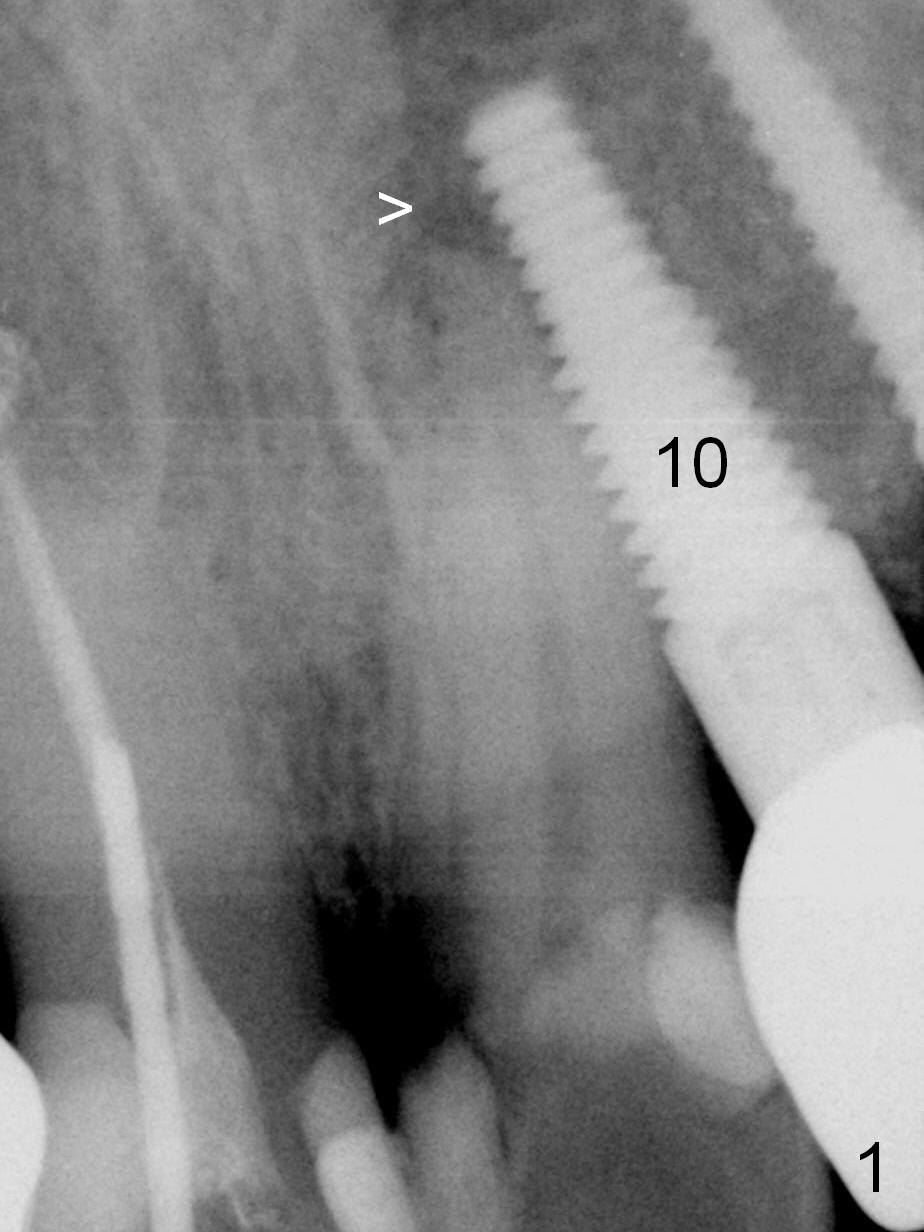

How to avoid apparent iatrogenic damage to the neighboring root? Preop PA shows approximation of these roots (Fig.2). Unfortunately the initial osteotomy is too mesial (Fig.3), which is unnoticed. When a 4.5x17 mm implant is placed, there is distal gap (Fig.4 <), while the mesial one is closed.